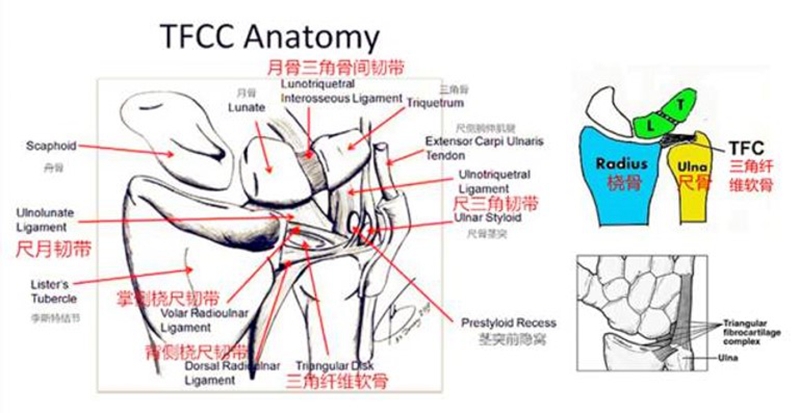

三角纤维软骨复合体(TFCC)是手腕最重要的纤维软骨-韧带复合结构,位于腕关节尺侧,分隔尺腕和远侧尺桡关节。常被称为是腕关节的“半月板”。

TFCC由以下韧带和纤维软骨组成:固有三角纤维软骨(TFC)、背侧桡尺韧带(DRUL)、掌侧尺韧带(PRUL)、尺三角韧带(UTL)、尺月韧带(ULL)、月三角韧带(LTL)、尺侧腕伸肌腱(ECU)鞘、尺侧副韧带(UCL)及半月板类似体(MH)。

固有三角纤维软骨

半月板同系物是关节盘远侧增厚的尺侧副韧带纤维形成半月板类似体,与关节盘共同起于尺骨背侧靠近尺骨的边缘,有尸解证实其附着于豌豆骨。

半月板同系物

血供

TFCC的周边约20%的区域(桡侧缘除外)有血供,中心约80%的区域无血供。这就决定了TFCC不同部位损伤后具有完全不同的愈合能力,同时也提示不同的分型需采取不同的治疗方式。早期明确损伤的性质以及撕裂的部位对临床治疗方法的选择具有关键性指导意义。